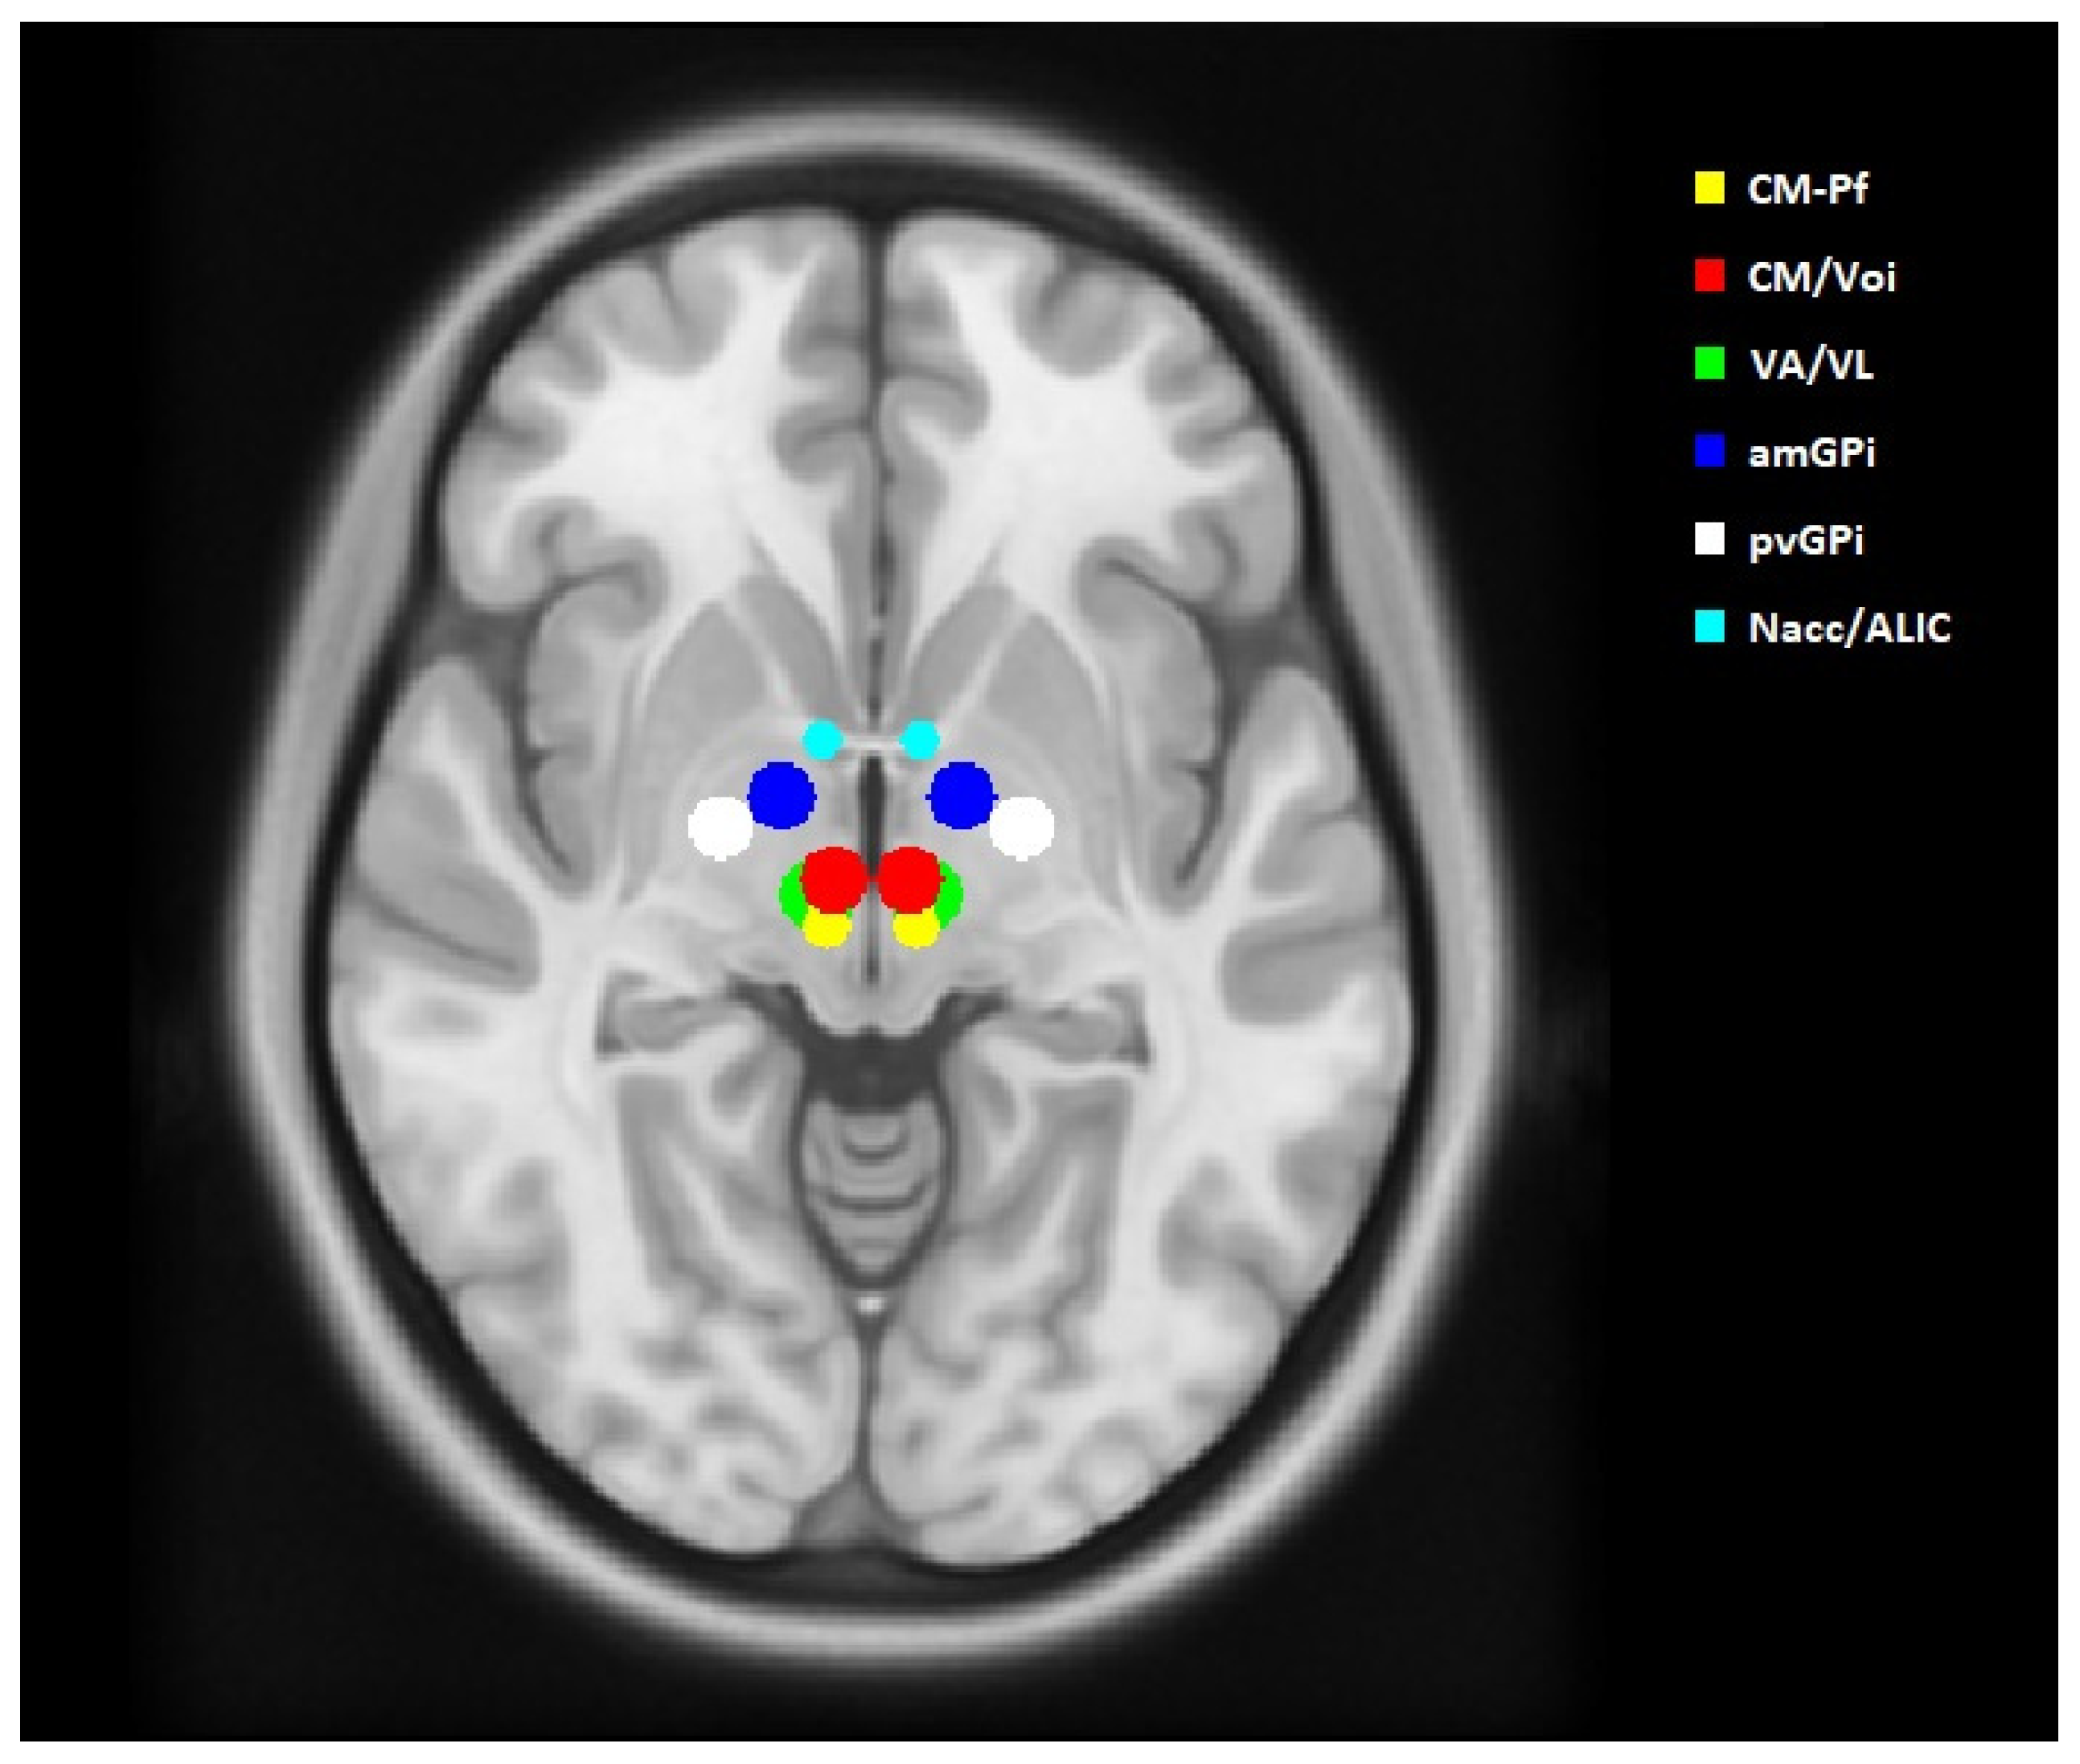

The coordinates were transferred to the standard asymmetric stereotactic space, using ICBM 152 MNI 2009b (MNI) []. We created sham volumes of tissue activated (VTAs) with a diameter of 5 mm in the MNI space at these targets. The sizes of the sham VTAs were derived from the actual stimulation parameters and postoperative CT scans of three of our GTS patients with the best clinical outcome (Table 1). Using the open-source software Lead-DBS (www.lead-dbs.org, Charité University Hospital, Berlin, Germany), the VTAs were estimated for these patients. The procedure has been described in detail in our previous publication []. The sham VTAs were transferred to each patient’s T2 sequence using FLIRT from the FSL v6.0 program (FMRIB Software Library, www.fmrib.ox.ac.uk/fsl) for affine linear matching, followed by deformable registration by advanced normalization tools (ANTs, http://stnava.github.io/ANTs/) []. The generated VTAs are shown in Figure 1.

Figure 1.

Anatomical location of the sham volumes of activated tissue (VTAs) in the ICBM 152 MNI 2009b space in axial view. All VTAs are spherical, with a diameter of 5 mm.